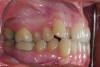

Layla Опубликовано 27 сентября, 2012 Поделиться Опубликовано 27 сентября, 2012 (изменено) Добрый день! Очень нужна консультация специалистов, т.к. я в полной растерянности. Так сложились обстоятельства, что процесс исправления прикуса я начала в другой стране и достаточно спонтанно.Мне 26, 5 лет. Была на консультации у 3 докторов, 2-ое из которых, не гляди на снимки с ходу сказали, что нужен аппарат RPE (в моем случае, как я поняла по фото, Хайрекс). 1 доктор советовал удалять. О хирургическом расширении никто из 3 не говорил.За 2 недели сделали аппарат и поставили почти 2 недели назад. Врач ничего толком не объяснила, ни планы лечения, ни возможные последствия, только сказала, что через пару дней я об аппарате забуду и что нужно раскручивать 3 раза в неделю.Я спросила, на сколько нужно расширить челюсть, она ответила -10 мм. Первые дни была сильная боль в области шестерок, на которых стоят кольца, жевать вообще не могла, да и до сих пор с трудом, челюсть не смыкается. Весь язык в ранах и не заживает , полоскания и сосательные таблетки от стоматита не помагают, слева верхние дуги врезаются в небо. результат -4 кг за неделю.Дикция ужасная, работа предполагает лекции на большие аудитории, не знаю , что делать. Пришлось самой начать изучать все в интернете.в итоге возникли вопросы по поводу адекватности лечения.Уважаемые специалисты, пожалуйста, посмотрите снимки , может вы сможете что-то порекомендовать.1. Нормально ли, что не попросили удалить 8-ки, хотя на нижней челюсти они в ужасном положении?2. Есть ли вероятность, что небный шов не разойдется и что делать в данном случае ? за почти 2 недели чувствую небольшое напряжение в переносице ( вроде как-то врач говорил, что искривлена) , щель между 1-ками не появляется.3. Какие могут быть негативные последствия расширения в моем возрасте?4. Можно ли в моем случае обойтись без удаления?5. Можно ли исправить прикус без хайрекса в моем случае или заменить его на что-то другое?6. Что делать с израненным языком, т.к. принимать пищу вообще не представляется возможным.7. И самое главное, как звучит мой диагноз?Родители просят название, а врач не сказала...Заранее огромное спасибо, очень жду ваших ответов и советов. Изменено 27 сентября, 2012 пользователем Layla Ссылка на комментарий

Force Опубликовано 30 сентября, 2012 Поделиться Опубликовано 30 сентября, 2012 34-36 - нормальное расстояние. В вашем случае экспансия может быть достигнута только с помощью брекет-системы. Расширение хайрексом чревато последствиями, три-четыре оборота назад обвчно делают. Рекомендую обсудить с вашим лечащим доктором. Диагноз ваш - бимаксилярная ретрузия, сужение зубоальвеолярных дуг, тесное положение зубов верхней и нижней челюстнй.Удаление восьмерок внизу критично. Ссылка на комментарий